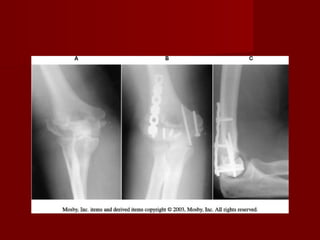

INTERCONDILEAS.

Clasificación de Mehne y

Matta es la que mejor

describe los hallazgos

transquirúrgicos.

   Cuando              los

fragmentos        estan

desplazados          es

preferible la reduccion

abierta.

   La cirugía se realiza

con mayor facilidad

en las primeras 24 a

48 horas.

    Vía  de abordaje de

Campbell, sus ventajas

son:

1.   Buena exposición de

todas las superficies

articulares.

2.   Lo cual permite libertad

de seleccionar el tipo de

fijación interna.

3. Una vez que el nervio

cubital     a      sido

identificado y retraido

medialmente, no hay

grandes     vasos     o

nervios en el sitio de

la insición